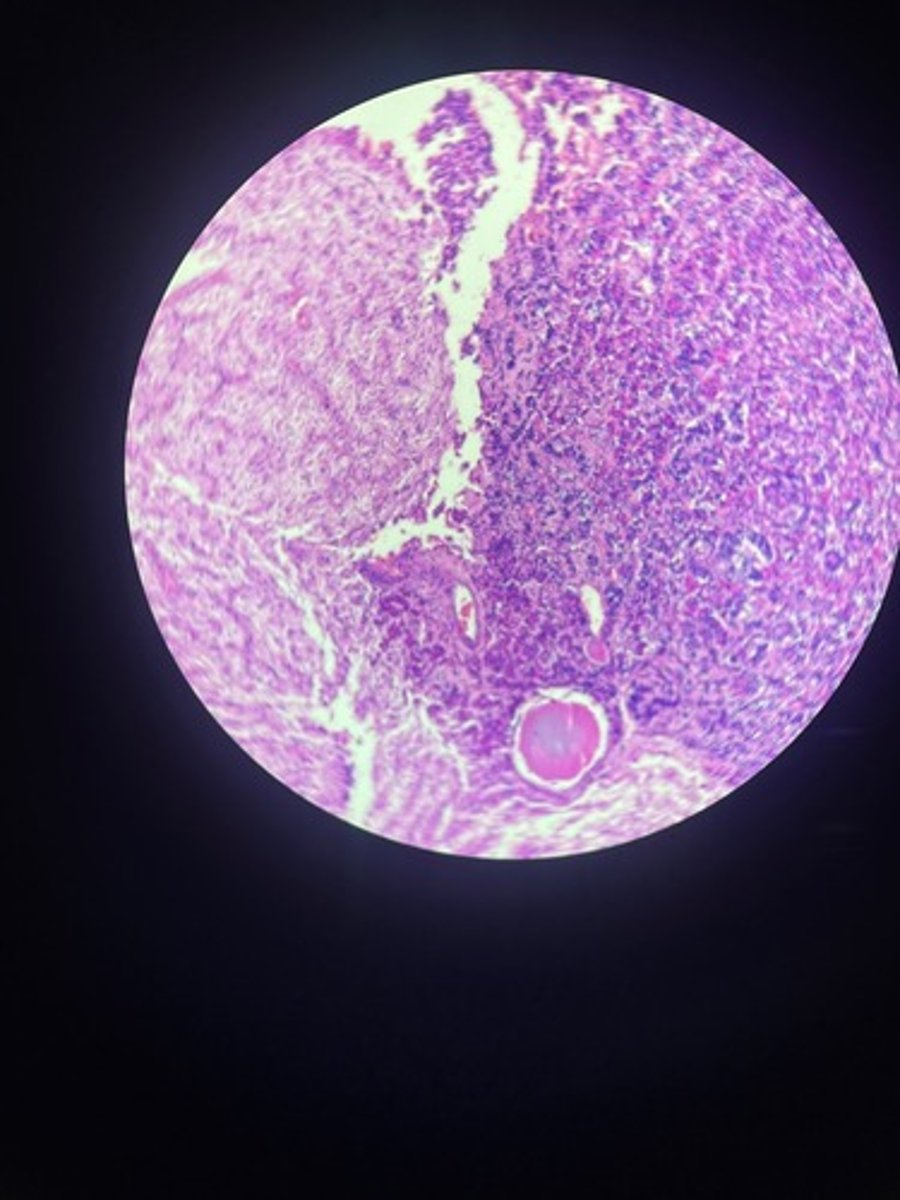

Thymus HE

Thymus HE

Thymus HE

Thymus HE

Thymus HE

Thymus HE

Thymus HE

Thymus HE